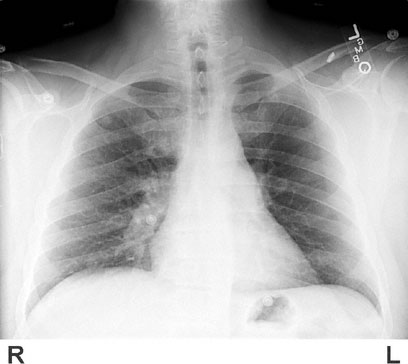

A 57-year-old man comes to the emergency department 2 hours after the onset of severe shortness of breath. He has not had any other symptoms. He has long-standing hypertension and type 2 diabetes mellitus. Current medications include lisinopril, metformin, and hydrochlorothiazide. He has never smoked. He is employed as a truck driver. His temperature is 37.4°C (99.4°F), pulse is 108/min, respirations are 24/min, and blood pressure is 126/82 mm Hg. Pulse oximetry on room air shows an oxygen saturation of 88%. Faint wheezes are heard on the left. There is an S4. Examination of the lower extremities shows 1+ edema bilaterally. An ECG shows sinus tachycardia. Arterial blood gas analysis on room air shows:

pH

7.44

Pco2

33 mm Hg

Po2

62 mm Hg

A chest x-ray is shown. Which of the following is the most appropriate next step in management?